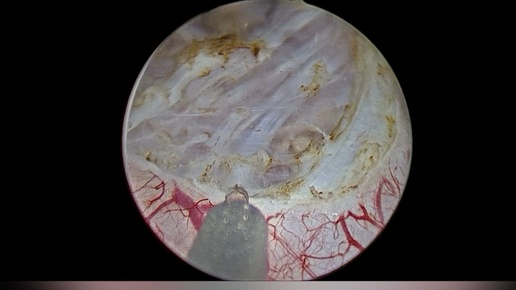

Лазерная en bloc резекция стенки млчевого пузыря с опухолью, иссечение рубцовой ткани и установка катетера-стента слева